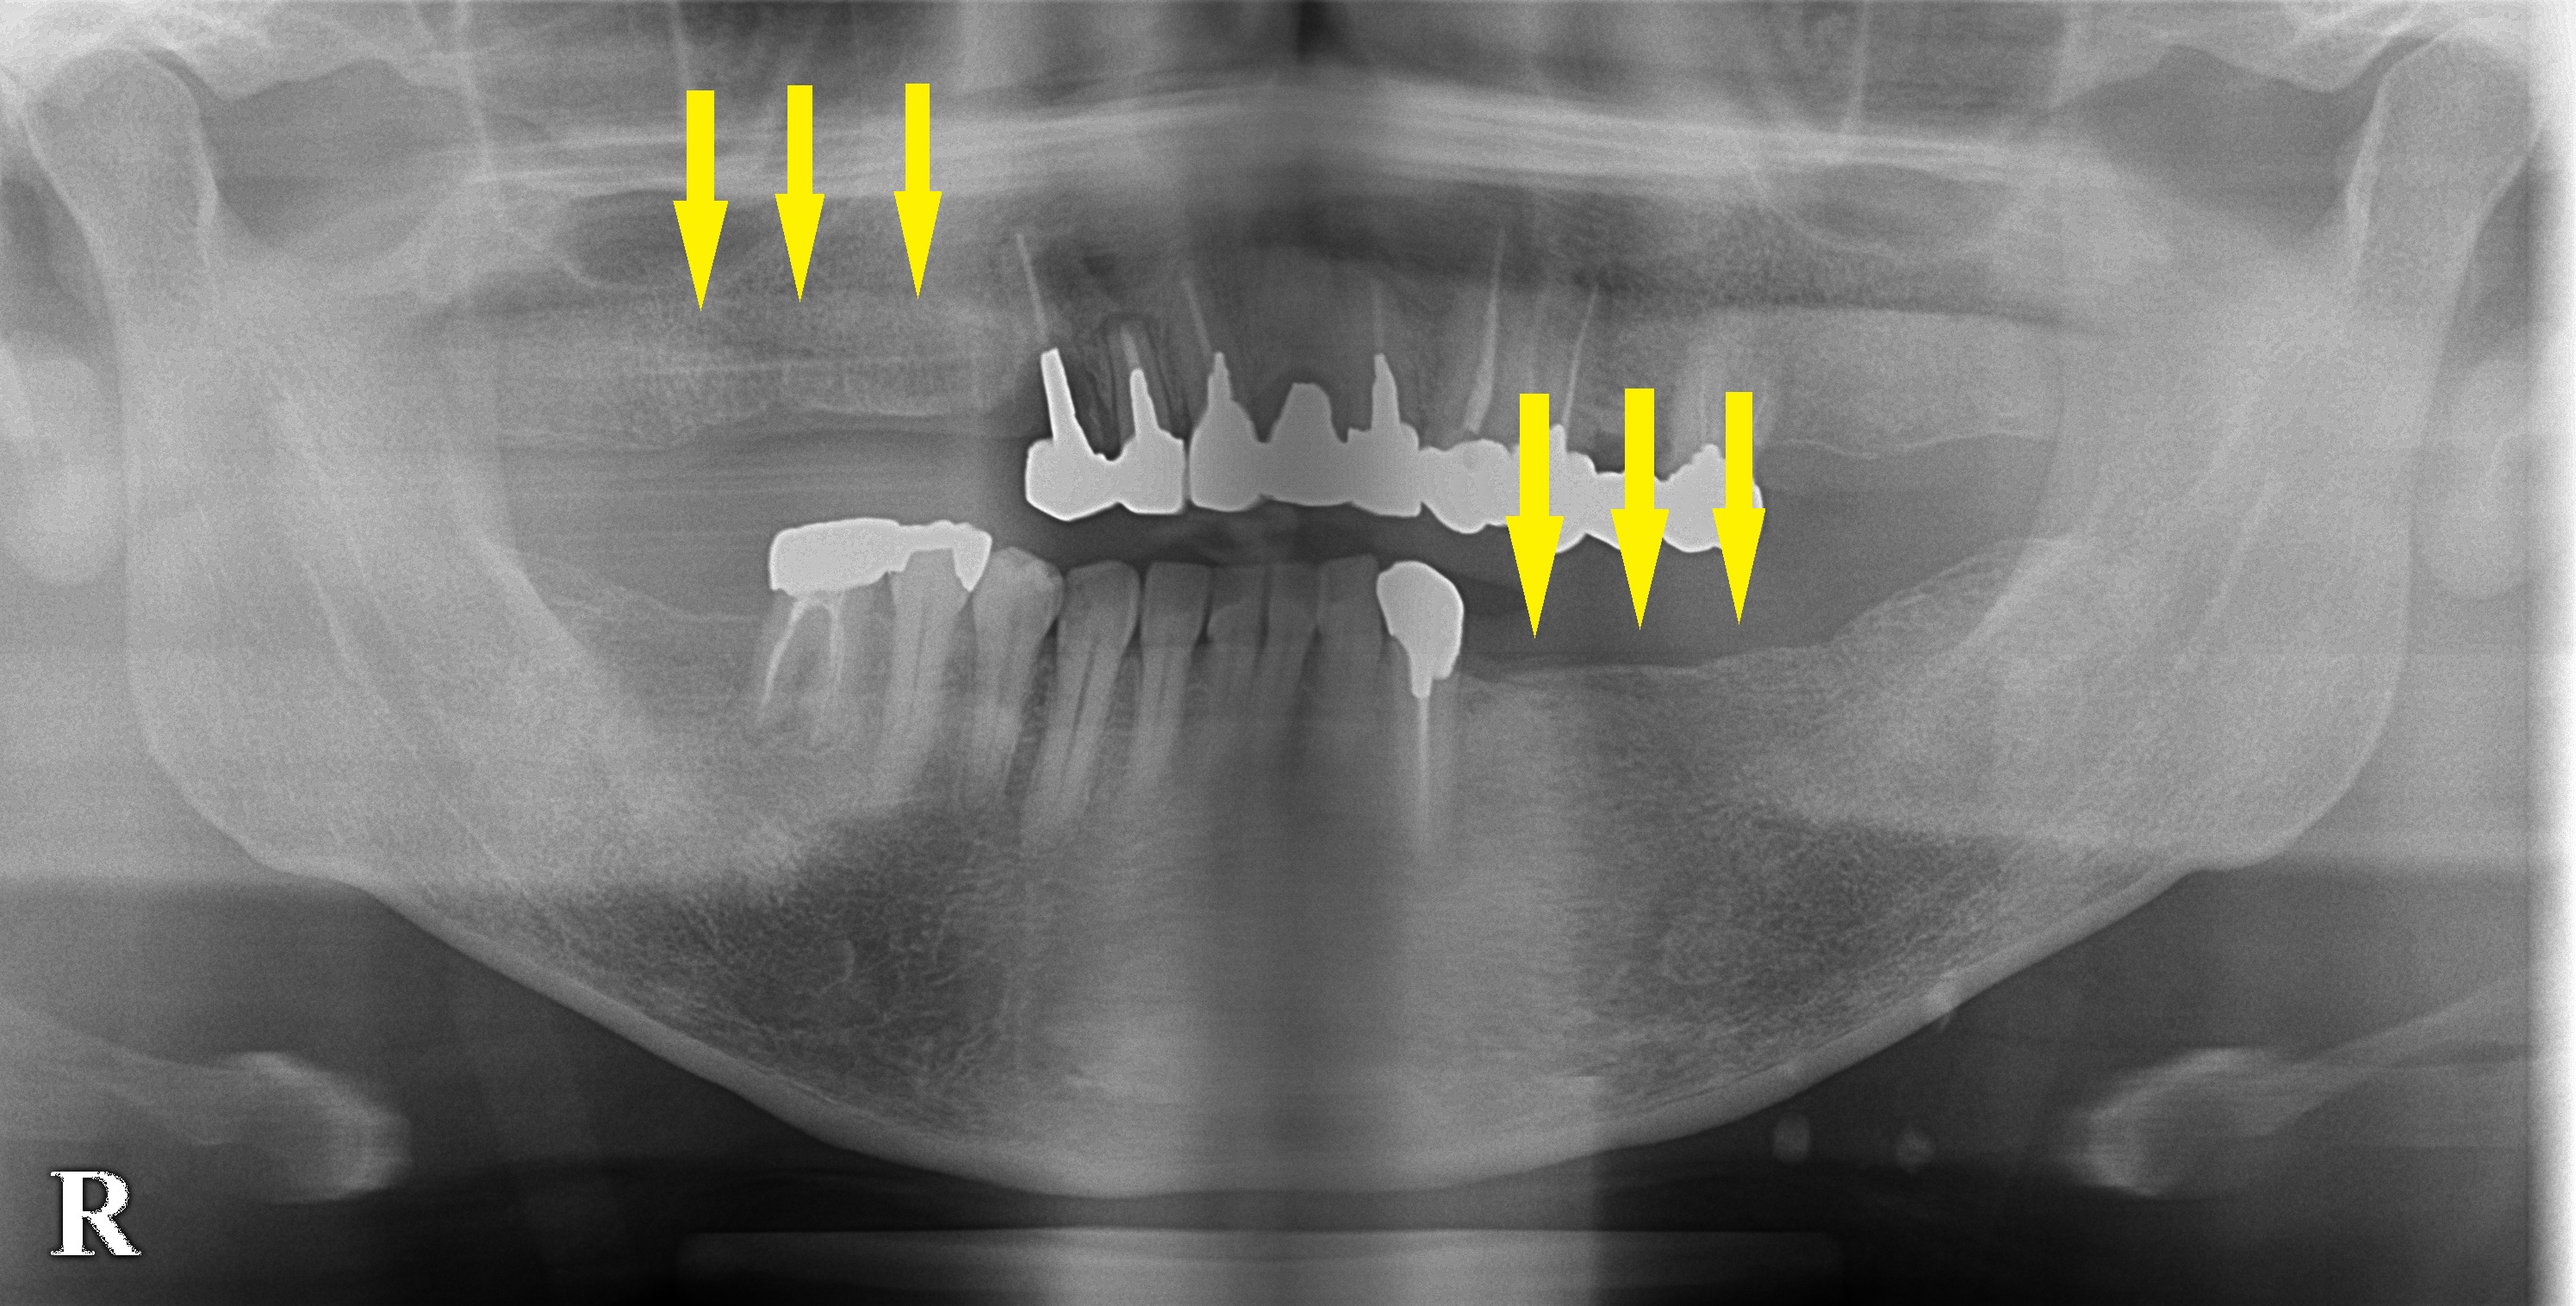

レントゲン写真、CTにて骨質がやや弱いようでしたが、骨量は十分でしたので、本日、まず左下顎に3本のインプラント埋入術を行いました。

実際の手術のドリリングで、やはり骨質がやや弱い感じでしたので、骨密度が上がるようなドリリングの工夫を行って埋入しました。

右上顎は、後日手術予定です。